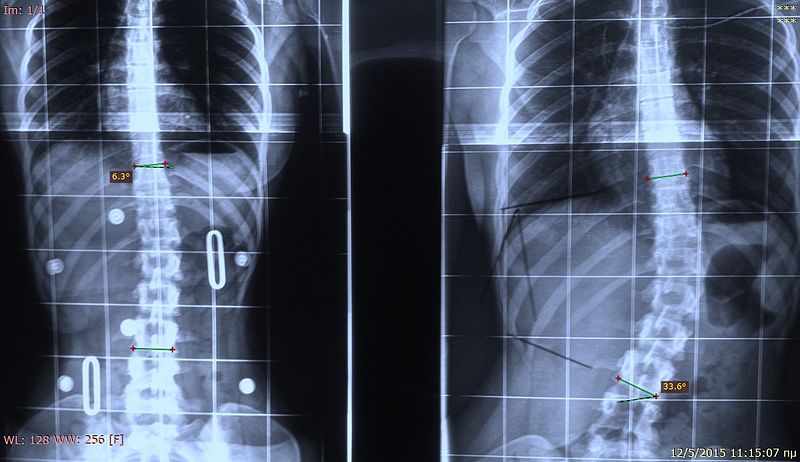

Il trattamento della scoliosi

Cos’è la scoliosi e come si tratta? La ginnastica correttiva e la ginnastica posturale sono un valido contributo.

La scoliosi nella fase evolutiva: una cattiva compagna

La scoliosi è ancora poco conosciuta e non ci sono miracoli per risolverla… ma la ginnastica posturale e correttiva può aiutare.